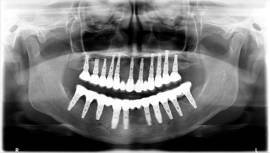

בלסת העליונה ביצענו עקירות כל השיניים בישיבה אחת עם הרמות סינוס משני הצדדים והתקנת 11 שתלים. בפגישה נוספת עבור הלסת התחתונה נעקרו גם כן כל השיניים עם ביצוע מיידי של 10 שתלים.

מייד בתום ההשתלות בכל לסת בוצעה העמסה מיידית עם גשרי אקריל זמניים שהוכנו מראש וסיפקו מענה תפקודי ואסטטי מצויין לתקופת ההמתנה.

לאחר 6 חודשים וקליטת השתלים באופן מלא, קיבלה המתרפאה גשרי חרסינה קבועים ברמת דיוק ואסטטיקה מושלמים.